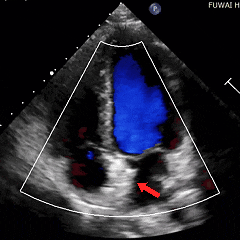

经胸右心声学造影:经左肘静脉注入震荡生理盐水(8mL生理盐水+1mL回抽静脉血+1mL空气经震荡制成),上腔、右房依次显影,造影剂完全充盈右心后,平静呼吸时,左房内即可探及微泡回声,约20-30个/切面/帧;瓦氏呼吸释放即刻,左房内探及微泡回声,不可计数。

术前静息状态经胸右心声学造影(中量)

术前瓦氏动作后经胸右心声学造影(大量)